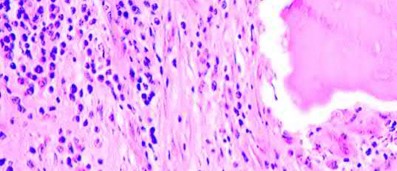

ALVAL (Aseptic Lymphocytic Vasculitis-Associated Lesions) is characteristic of adverse local tissue reactions (ALTR) in metal-on-metal hip implants. It is driven by a Type IV (delayed) hypersensitivity reaction to metal ions (like cobalt and chromium). This cell-mediated response involves the activation of CD4+ Th1 cells and is characterized histologically by a dense perivascular lymphocytic infiltrate, tissue necrosis, and the formation of pseudotumors, distinguishing it from the simple macrophage-mediated foreign body response seen with conventional polyethylene wear debris.